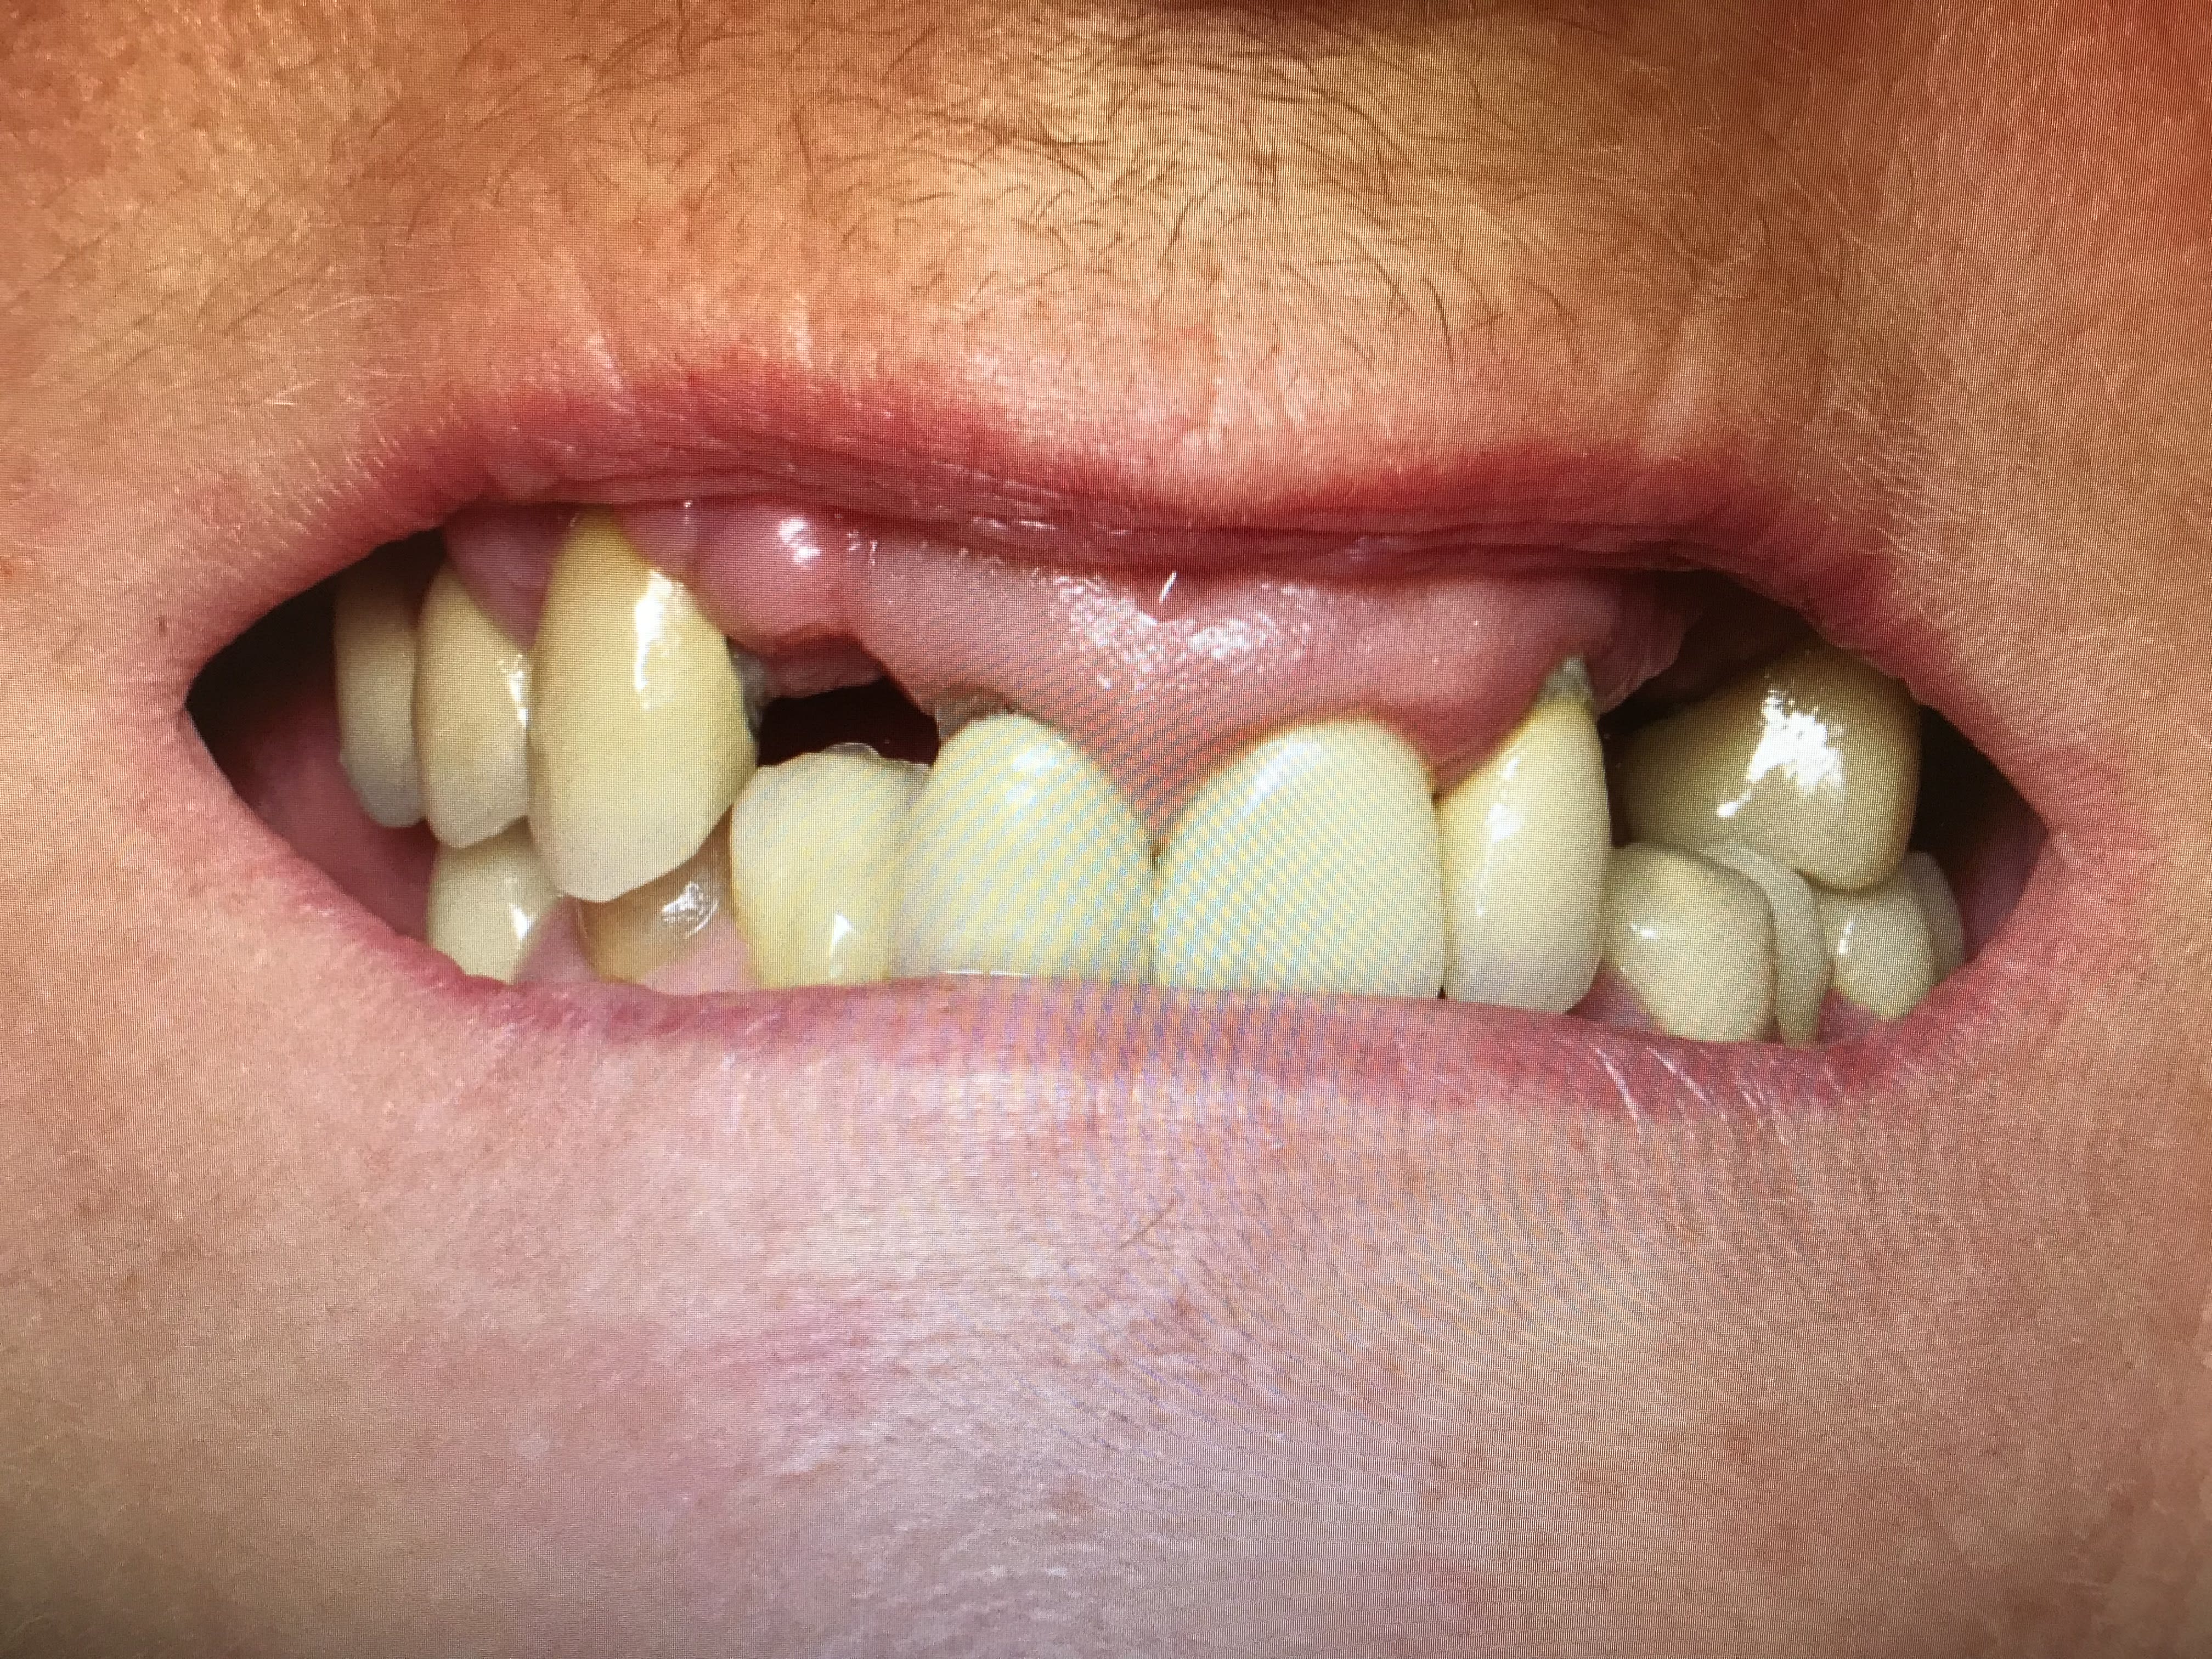

Patiente avec pilier de bridge 13 fracturé + 15 paro mobile + 25 paro mobile + 22 légèrement mobile. Les seules dents "viables" sur l'arcade sont 11, 21 et 22 et la 12 a été extraite entre temps.

Patiente avec grosse supraclusion et sourire gingival.